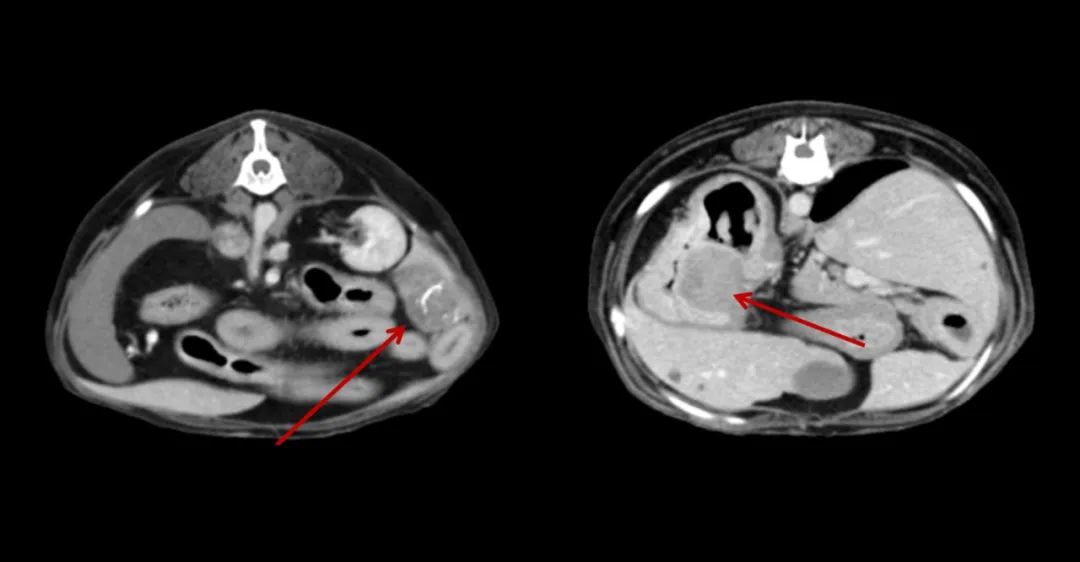

7歲,38kg的金毛狗近期總是嘔吐,CT全身平掃+增強,發(fā)現肝和胃占位性病變。

640 (2).jpg